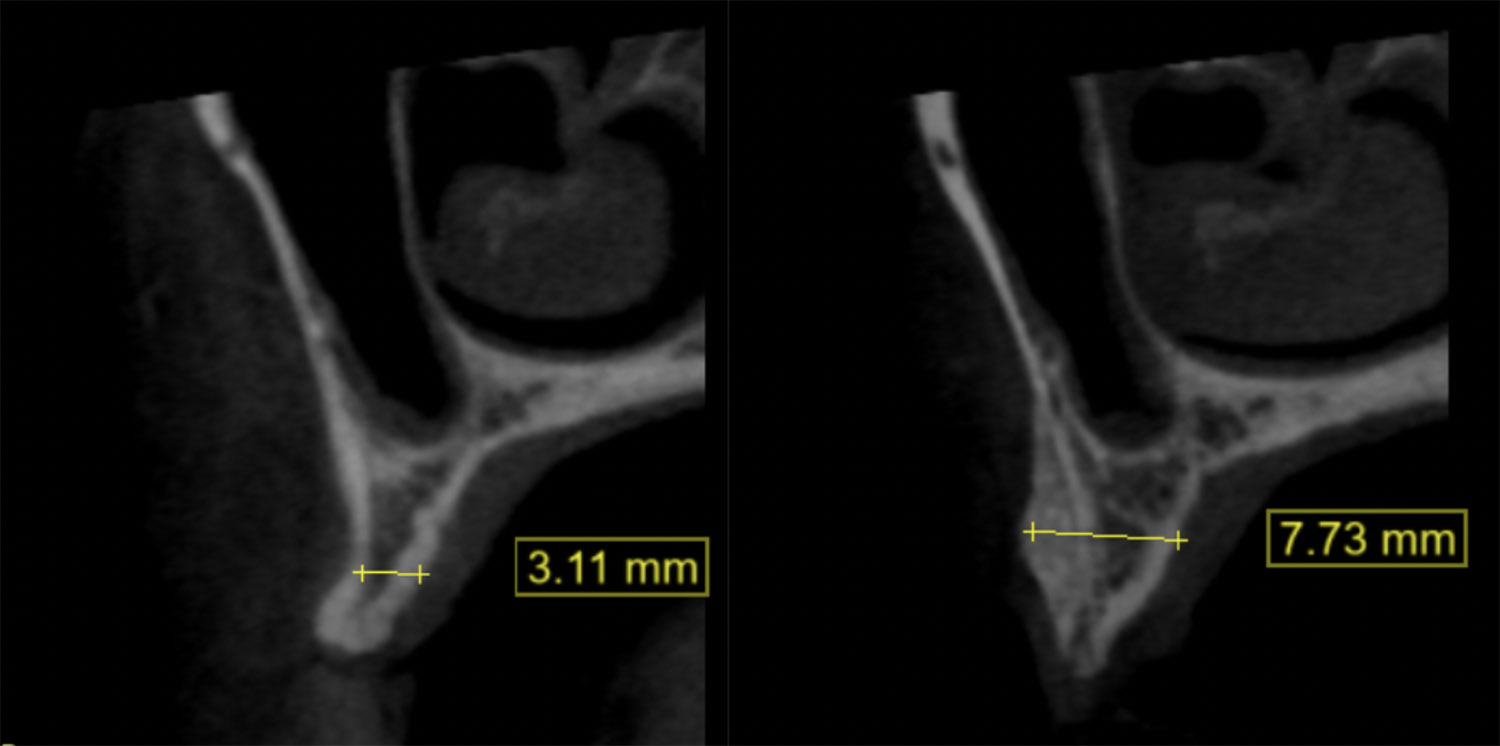

左圖代表的是補骨手術前的電腦斷層圖,可以看到最窄的部分寬度只有約3釐米,右圖是補骨手術後6個月的電腦斷層圖,骨頭的寬度有顯著的成長到7釐米,為後續的植牙品質提供良好的保障。